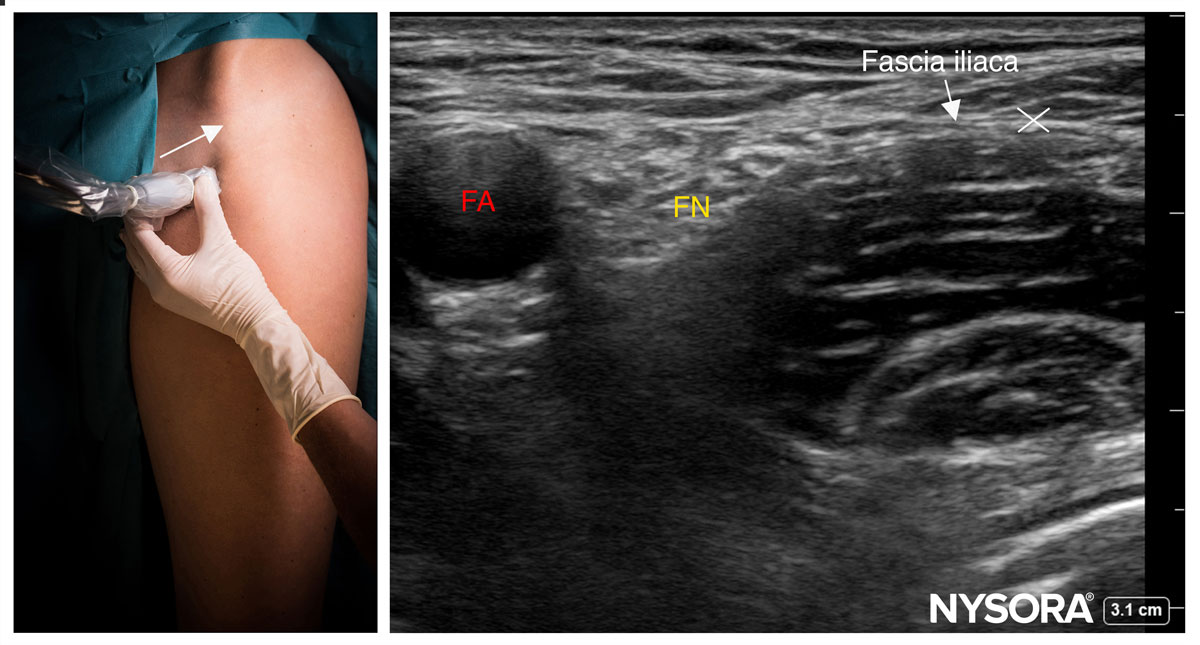

Fascia iliaca block – infrainguinal approach

Fascia iliaca block – suprainguinal approach

Femoral nerve block